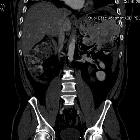

Metastatic

well-differentiated neuroendocrine carcinoma of the pancreas: case report and review of literature. Computed tomography (CT) of the abdomen and pelvis. A large 4.7 centimeter (cm) lobulated hypodense mass is shown in the region of the porta hepatis likely secondary to the tumor mass.